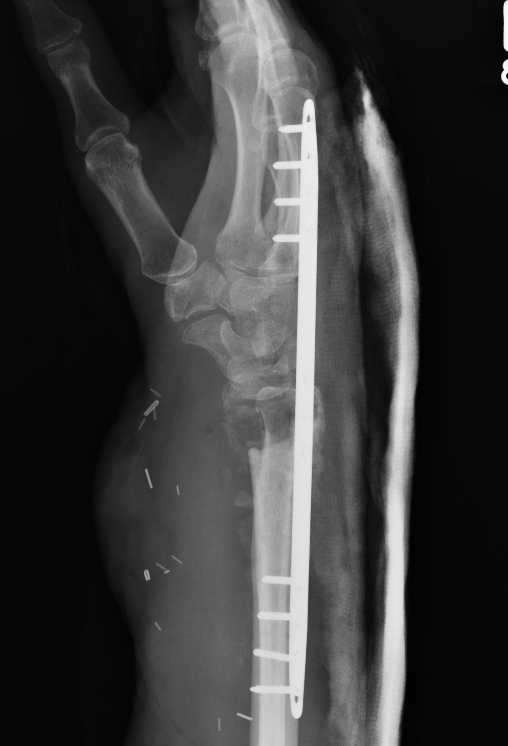

Malunion

www.boneschool.com/distal-radius-fracture-malunion